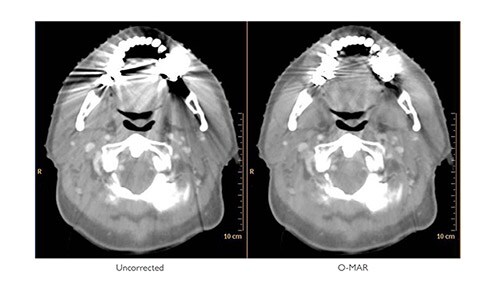

Metal artifacts in CT images, manifesting as dark streaks (green arrows). O-MAR enhances the visualization of structures by iteratively calculating interpolated values which simulate tissue.

With O-MAR, not only are severe streaking artifacts reduced, substantial portions of previously obscured anatomy can now be visualized. Since the system will always reconstruct both sets of images whenever O-MAR is selected, the uncorrected images are readily available. Although the main purpose of O-MAR is to address artifacts arising from orthopedic metal, it is also effective for some kinds of non-orthopedic metal, e.g. dental fillings.